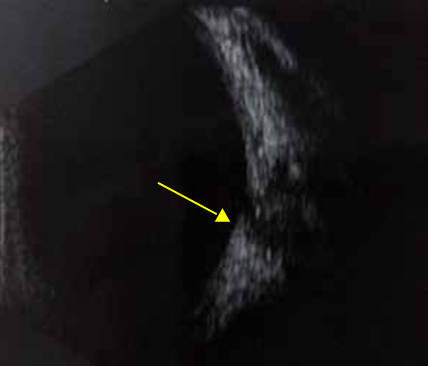

Uvéite Postérieure

L’uvéite postérieure est la manifestation inflammatoire la plus fréquente et la plus grave. Elle est marquée principalement par une hyalite (figure 2), d’intensité variable, pouvant être responsable d’une baisse importante de l’acuité visuelle avec un fond d’œil complètement masqué (4).